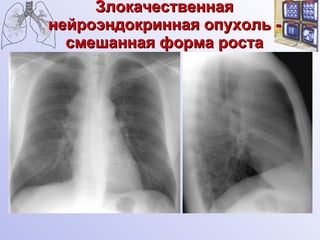

Злокачественная нейроэндокринная опухоль - смешанная форма роста